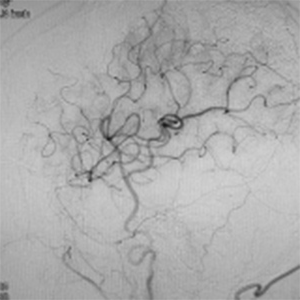

バイパス術で増加した脳血管

バイパス術により脳血流が正常化